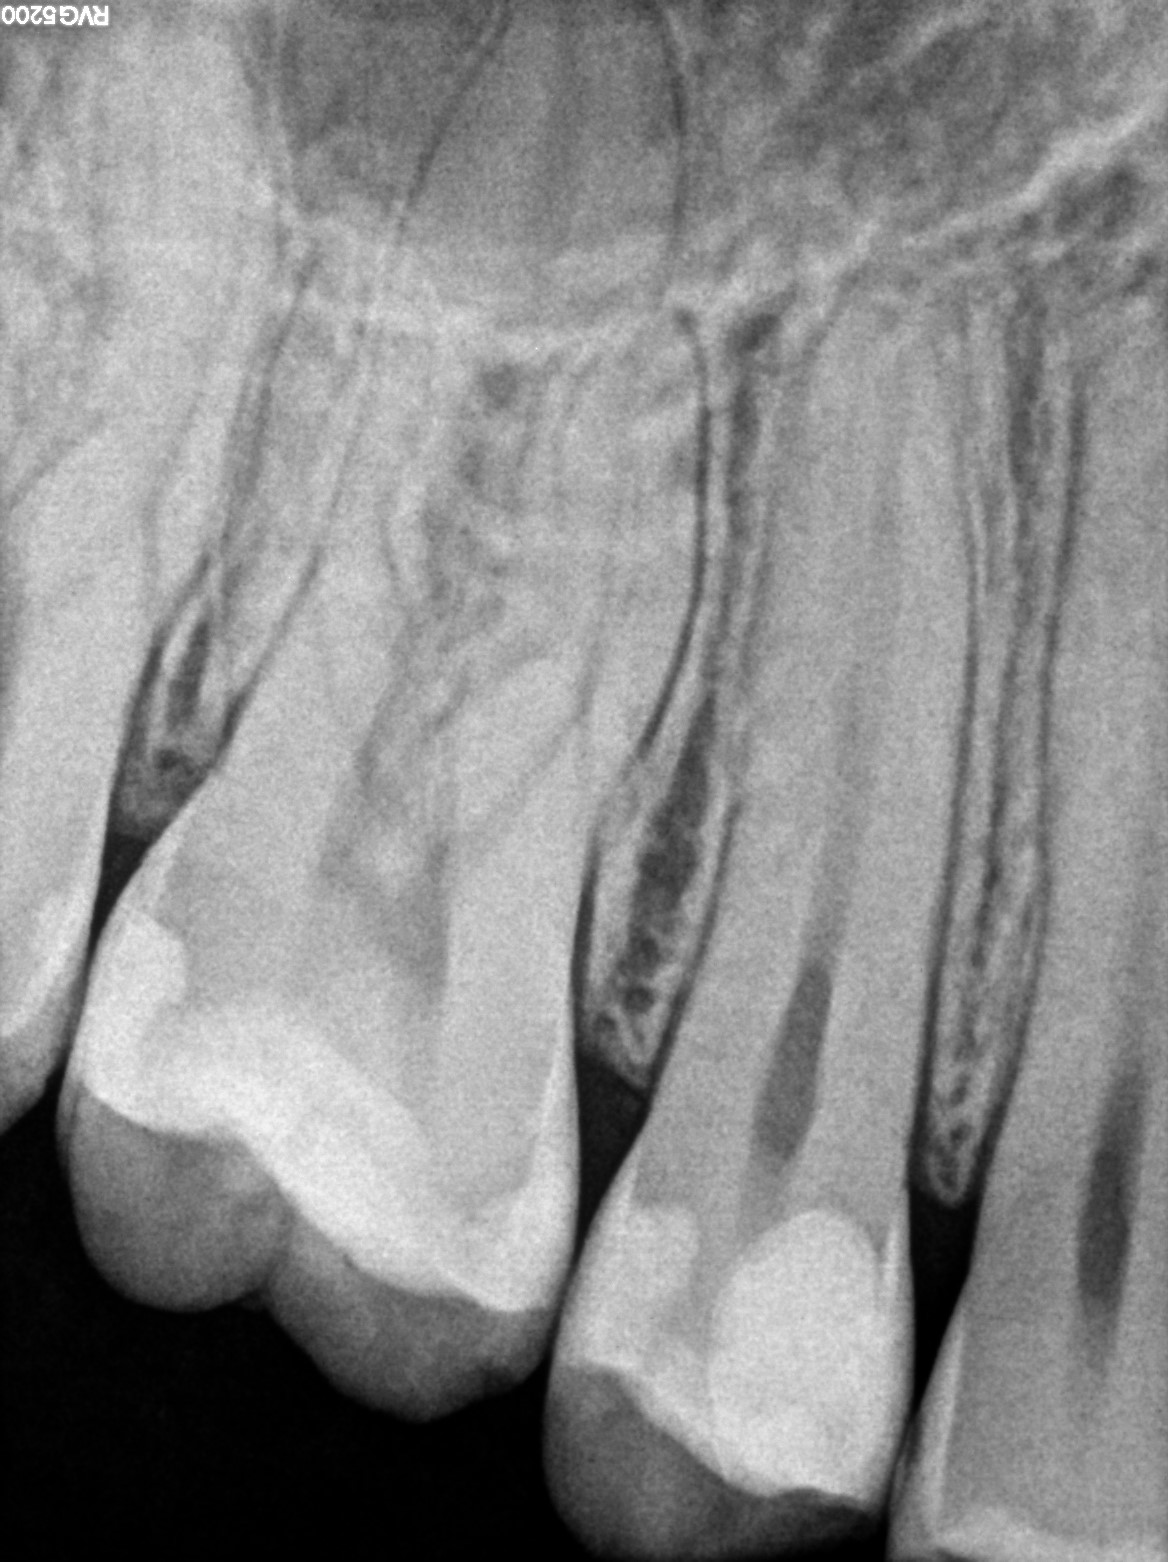

Zgodnie z wytycznymi ESE dotyczącymi leczenia przyżyciowego leczenia miazgi, kolejna wizyta kontrolna odbyła się po 6 miesiącach (12 miesięcy od przykrycia bezpośredniego miazgi) (2). Ząb 15 nie bolał samoistnie, wykazywał prawidłową reakcję na chlorek etylu. Na zdjęciu kontrolnym wykonanym w systemie radiografii cyfrowej przyzębie wierzchołkowe nie wykazało cech patologii (ryc. 13).

Ryc. 13. RVG kontrolne po 12 miesiącach od zabiegu bezpośredniego przykrycia miazgi zęba 15.